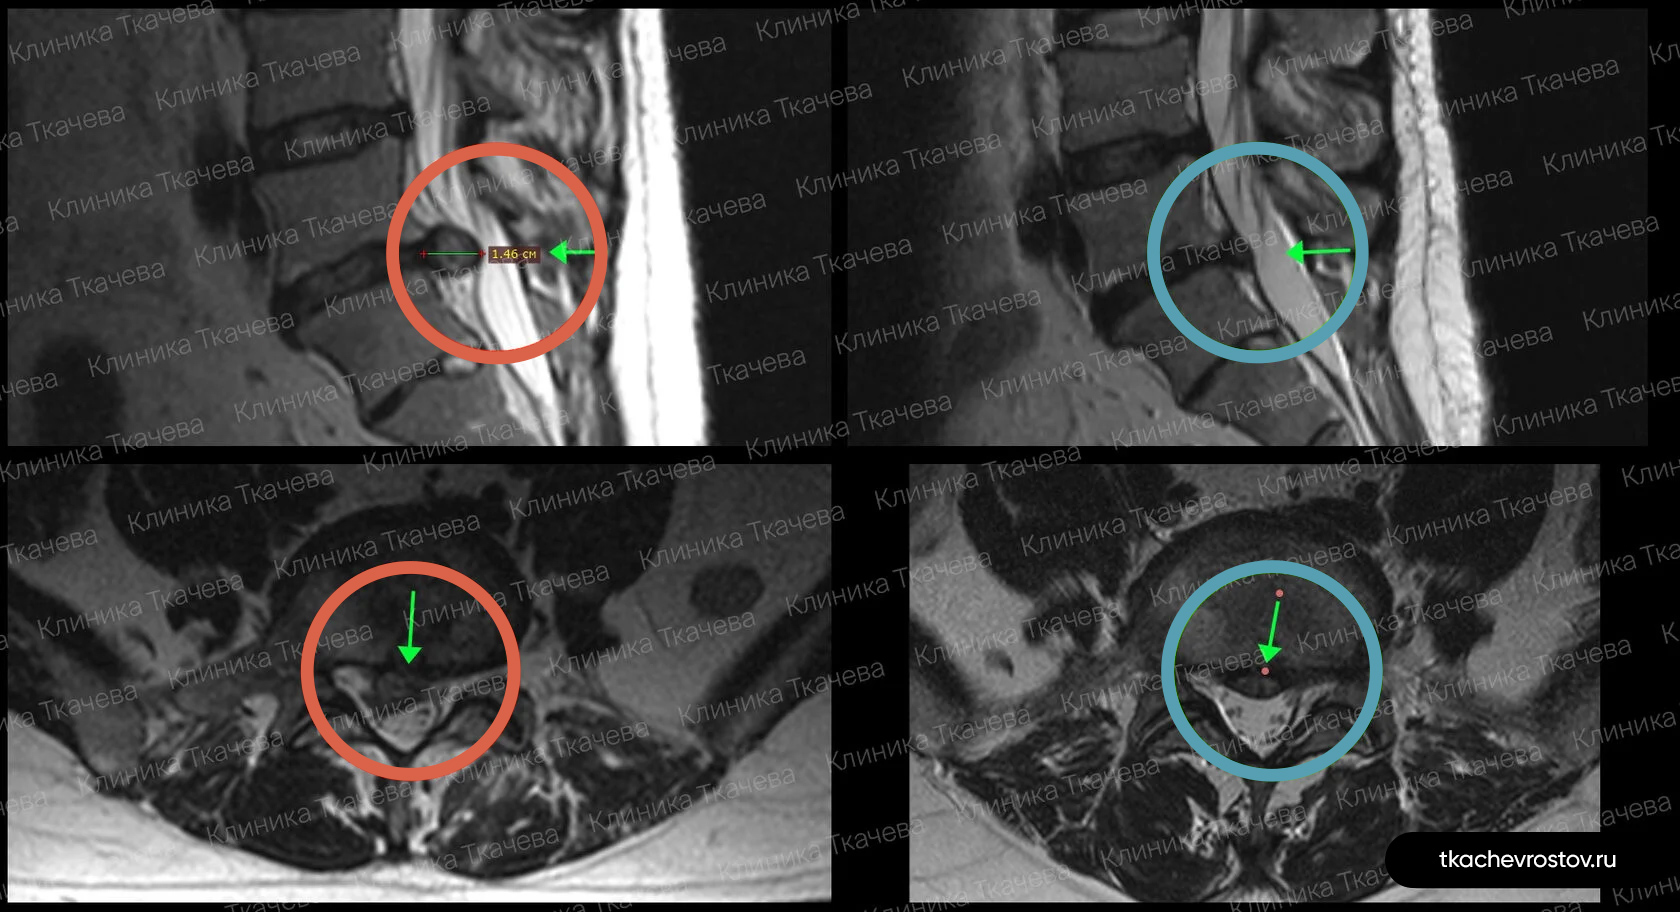

Грыжа в поясничном отделе L4-L5

Мужчина. Межпозвонковая грыжа в сегменте L4-L5 1.5 х 1.7 см с абсолютным стенозом позвоночного канала. Никакое лечение не помогло, отправили вначале к психиатру, а потом к нейрохирургу.

ДО:

- Интенсивная боль в пояснице, с эпизодическими прострелами

- Ограничение движений в пояснице

- Нарушения сна

- Снижение бытовой и социальной активности

ПОСЛЕ 1 курса:

✓ Наступила частичная резорбция грыжи

✓ Наступило улучшения общего состояния.

ПОСЛЕ 2 курса:

✓ Наступила полная резорбция грыжи

✓ Небольшое восстановление высоты межпозвонкового диска (регенерация пульпозного ядра)

Лечение грыжи заняло 8 месяцев. Было проведено 2 курса лечения по 12 дней.